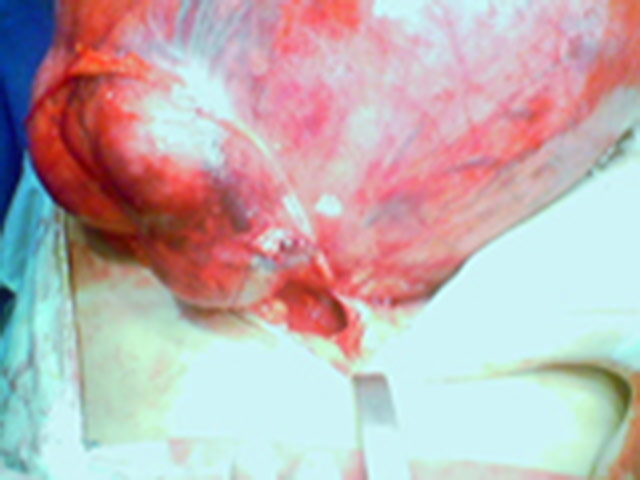

Fibroma

Vemos grande fibroma em nulípara.

Outro ângulo vendo o ovário esquerdo.

Aproximação do fibroma.

Peça cirúrgica.